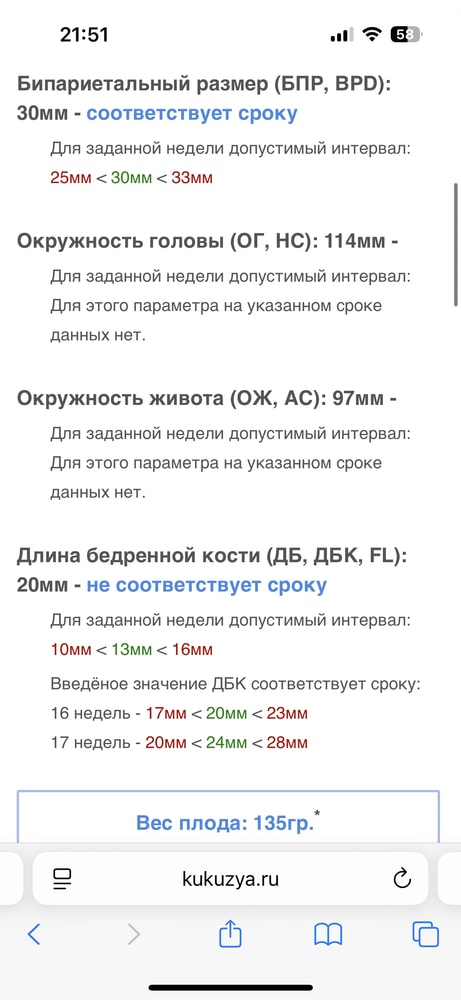

Как может быть 132 гр когда по всём таблицам 50-70 гр. Рост не указан. Сказали всё в норме, соответствует норме. Но мне не понятно.

Странное УЗИ, вес плода 15 нед и 0 дней

Вбейте свои показатели в калькулятор расчета веса. Если покажет тоже самое, значит ошибка либо в измерениях, либо в сроке. На 3 недели не видела чтобы спешили дети, мой на 2 спешит, но недели с 20 только

Элементарно может быть. Может чуть с опережением развивается (особенно отдельные части) + вам наверняка доверительный интервал поставили (133+/- сколько-то там)